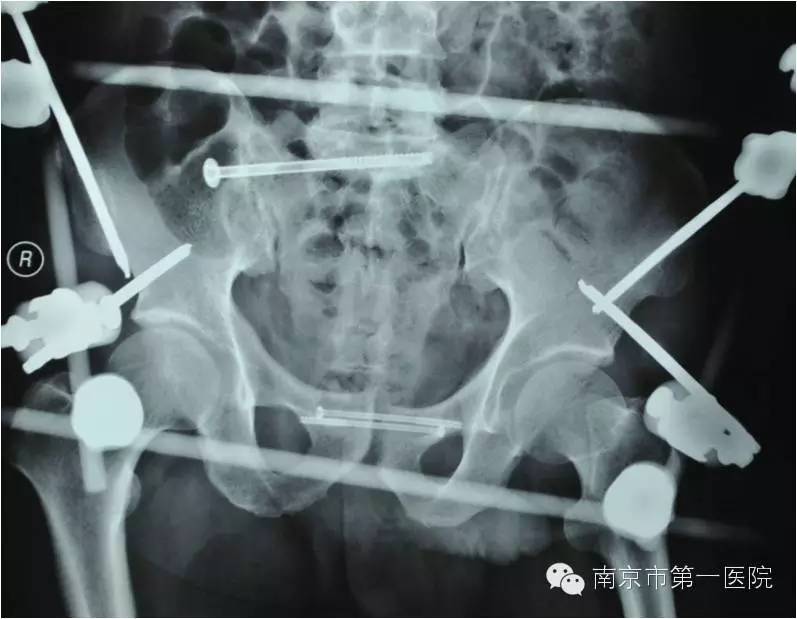

我院骨科专家梁斌接到通知后,开通多发伤绿色通道,迅速召集科内骨干医生进行术前讨论、制定手术计划。考虑到患者创伤严重、出血量大,必须最大程度地减少手术伤口,梁主任决定立刻采取微创技术进行骨盆闭合复位支架外固定术。

术中,主刀医生操作技术娴熟,争分夺秒,有条不紊地进行着各项操作。经过1个小时,手术顺利结束,成功修复了患者重度骨折的骨盆。据悉,整个手术过程中,创伤小、出血量低,切口大小也仅有1-2cm左右。